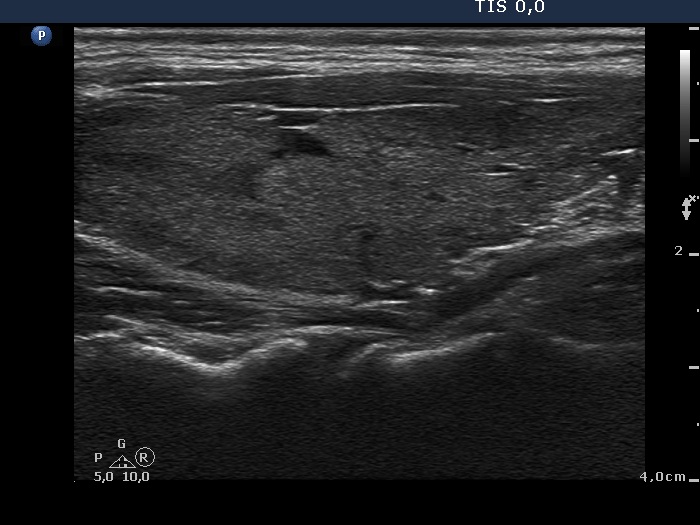

Case 1380 (ultrasonographic picture 5)

Left lobe, longitudinal view.